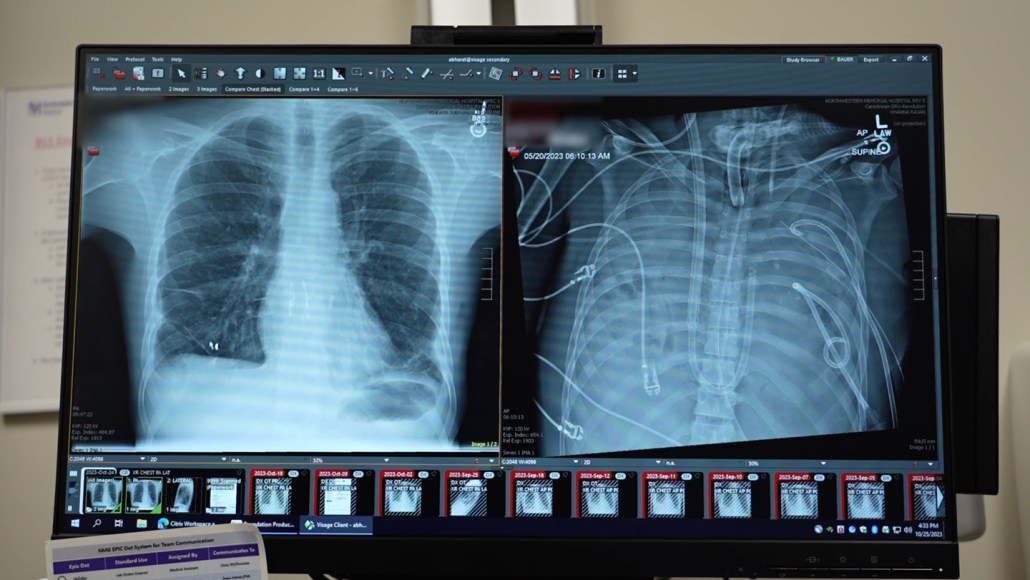

Two X-rays side by side show a man's new lungs and his old ones, which wew so damaged they could not hold air.

These X-rays are from a man who was kept alive for two days on a total artificial lung. On the right are the old lungs, which are diseased and have no visible air. On the left are his new, healthy transplanted lungs.

Northwestern Medicine